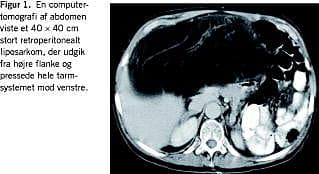

Sygehistorier

I. En 70-årig kvinde blev henvist til onkologisk behandling i juli 2003 pga. et 40 × 40 cm stort, inoperabelt LPS. Patienten havde haft utilsigtet vægtøgning og en fornemmelse for oppustethed i toethalvt år. Gastroskopi, ultralydskanning og koloskopi × 3 viste alle normale forhold, idet man dog fandt divertikulose i colon. Patientens symptomer blev tolket som colon irritabile og habituel vægtøgning. Efter ønske fra patienten blev der senere foretaget computertomografi (CT) af abdomen, og på CT'en sås en meget stor retroperitoneal tumor. Der blev foretaget laparotomi på et lokalsygehus, og patienten blev der vurderet til at være inoperabel. En peroperativ biopsi viste et højt differentieret LPS. Efter seks serier kemoterapi med doxorubicin fik patienten tiltagende tryksymptomer, og ved CT fandtes objektiv progression af tumoren. Patienten blev henvist til kirurgisk revurdering. Der blev udført en radikal excidering af en 40 × 40 cm stor retroperitoneal tumor, vægt 5.870 g. Tumoren udgik fra højre flanke og pressede tarmsystemet mod venstre (Figur 1 ). Det postoperative forløb var ukompliceret. Patienten blev fulgt med kvartårlige billeddiagnostiske undersøgelser og var ved seneste magnetiske resonans (MR)-skanning to år efter operationen recidivfri.